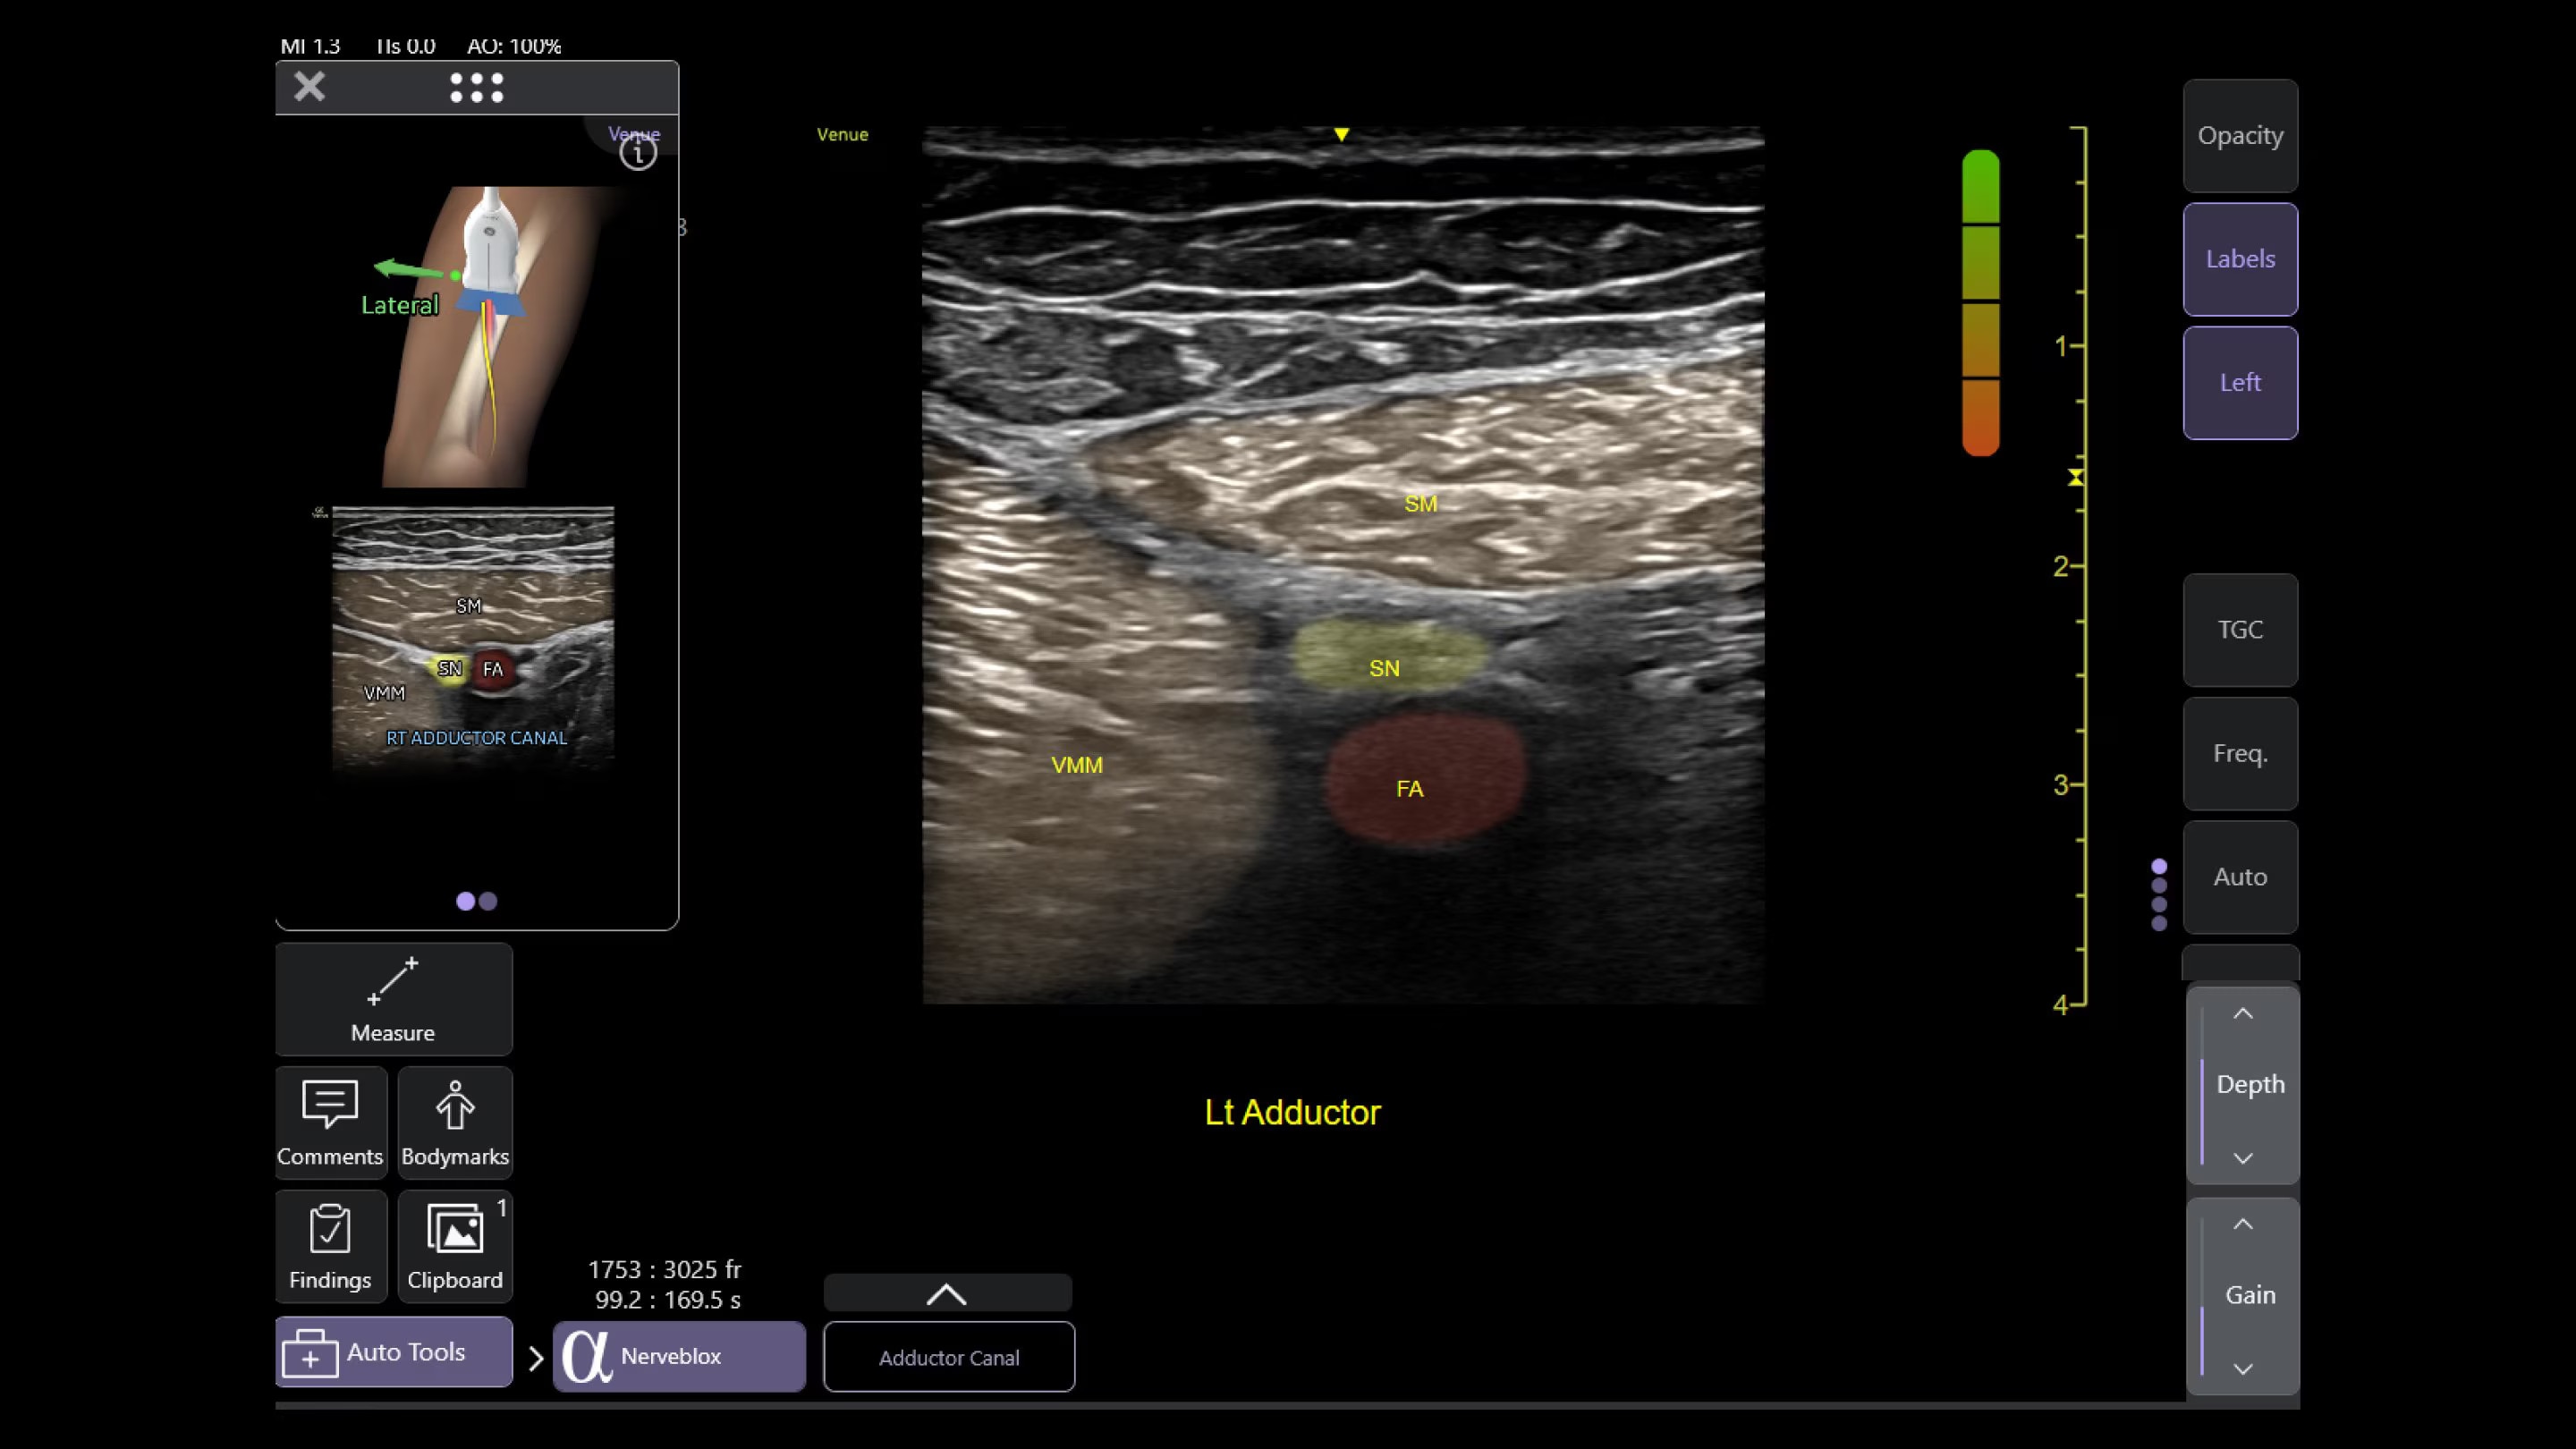

Automated tools

Simplify your workflow with AI-enabled clinical tools.

Helping drive consistency from user to user (whether one is an ultrasound novice or expert), Venue Fit features AI-enabled resources that help clinicians work smarter and more efficiently. Utilizing proprietary algorithms, we synthesize data from numerous patients to ensure accurate calculations for clinical confidence.